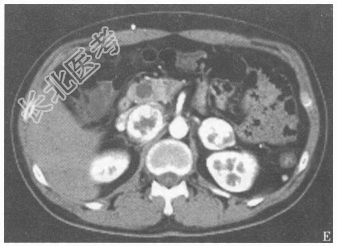

- 简答题3、患者的腹部+盆腔CT检查结果见图4、图5。患者目前可能的诊断是